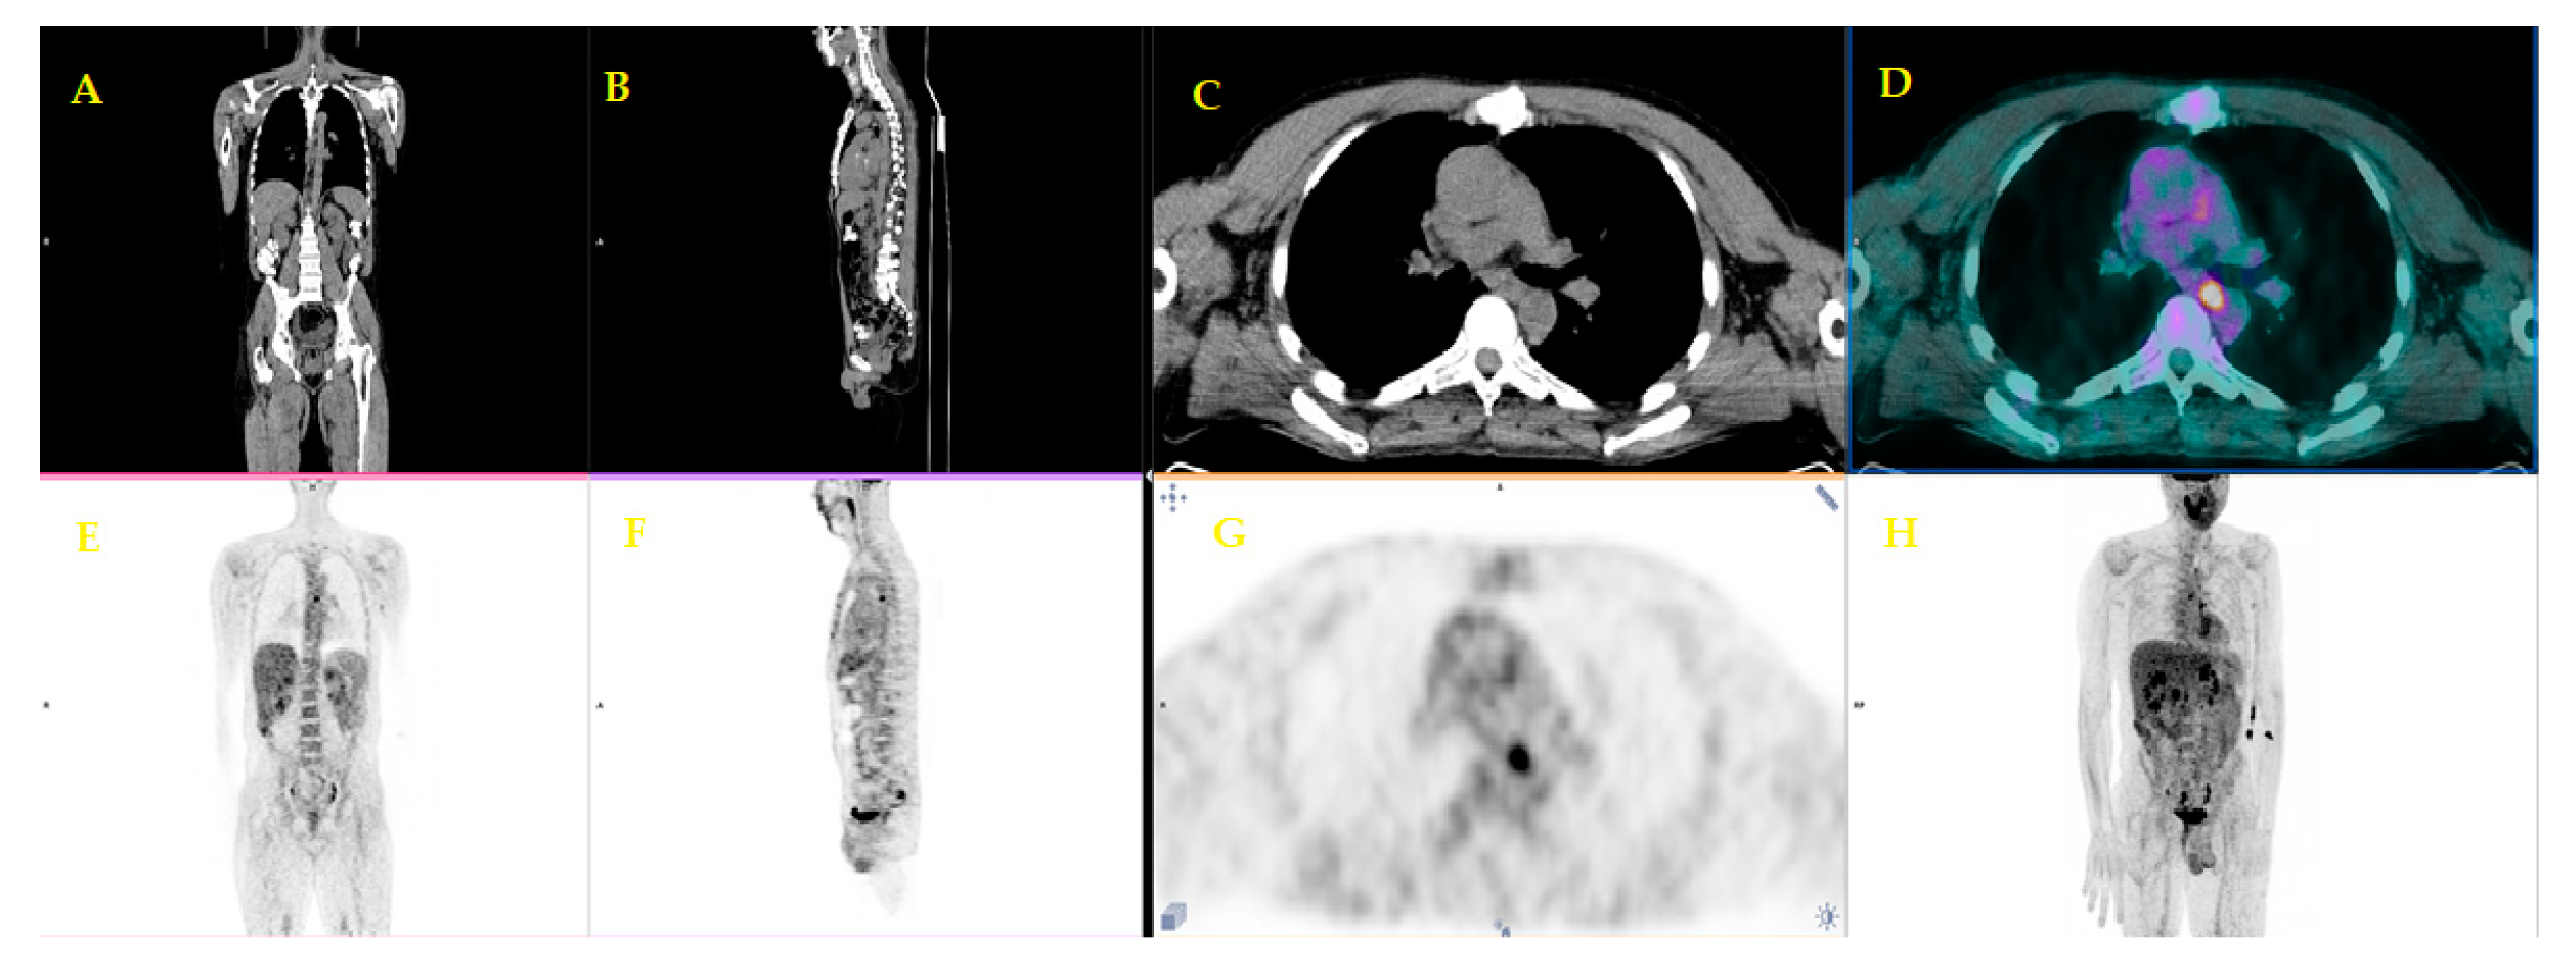

| 7 | Strobel et al. [22] | 2015 | Retrospective study | 50 (64.3) | Preoperative staging biopsy-proven pancreatic adenocarcinoma | The one-stop-shop imaging approach is superior to unenhanced PET/CT in defining the resectability of PDAC, improving the detection of distant metastasis. |